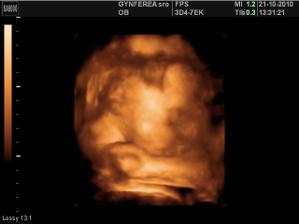

tijuska krasna fotecka